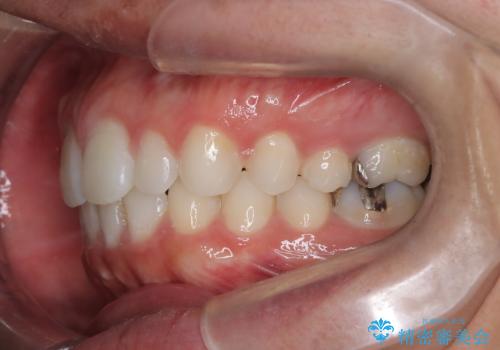

【前突症例】前歯を下げたい

- 前歯の隙間と口元を主訴に来院されました。

インビザラインにて治療を行いきれいな歯並びをつくることができました。

奥歯の噛み合わせもきちんと仕上げることができました。